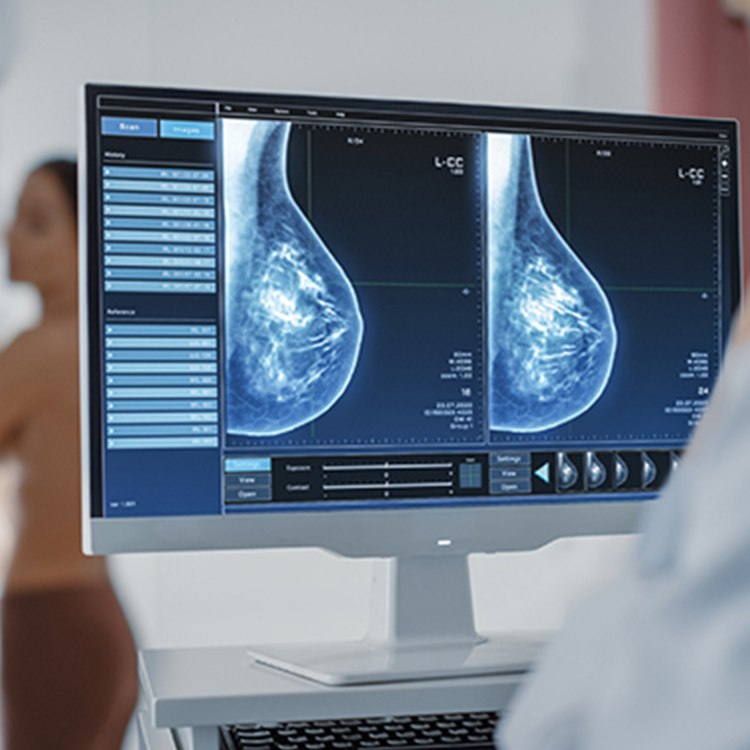

Gelişmiş Teknoloji, Net Sonuçlar.

Yüksek çözünürlüklü cihazlar ve güncel radyoloji teknikleri sayesinde daha ayrıntılı görüntüler elde edilir, tanısal doğruluk en üst seviyeye taşınır.